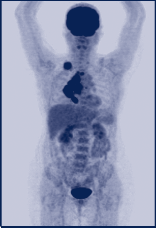

Jeweils MIP-Darstellungen mittels FDG-PET/CT. Bild 1 zeigt die Ausgangssituation eines Patienten mit M. Hodgkin rechts supraclaviculär, mediastinal und pulmonal vor Chemotherapie. Bild 2zeigt denselben Patienten nach erfolgter Chemotherapie und gutem Ansprechen auf die Therapie somit nur noch residuelle Weichteilgewebsvermehrungen in den ehemaligen Lymphommanifes- tationen, jedoch ohne Nachweis von vitalem Restgewebe.

Lymphome:

In der Diagnostik der Lymphome spielt die PET/CT eine wichtige Rolle. Sowohl bei Non-Hodgkin- als auch bei Hodgkin-Lymphomen wird sie insbesondere zum frühen Nachweis eines Therapieansprechens eingesetzt. In einer aktuellen Studie konnte gezeigt werden, dass die Sensitivität im Restaging von agressiven B-Zell Non-Hodgkin-Lymphomen mittels PET/CT bei ca. 80-90 % liegt, verglichen mit einer Sensitivität von ca. 40-50% in der alleinigen CT-Diagnostik. Seit Oktober 2010 werden unter bestimmten Bedingungen (Interimsstaging nach 2-4 Zyklen Chemotherapie bei Hodgkin- und agressiven Non-Hodgkin-Lymphomen zur Beurteilung der Therapiefortsetzung) die Kosten für die PET-Diagnostik übernommen.